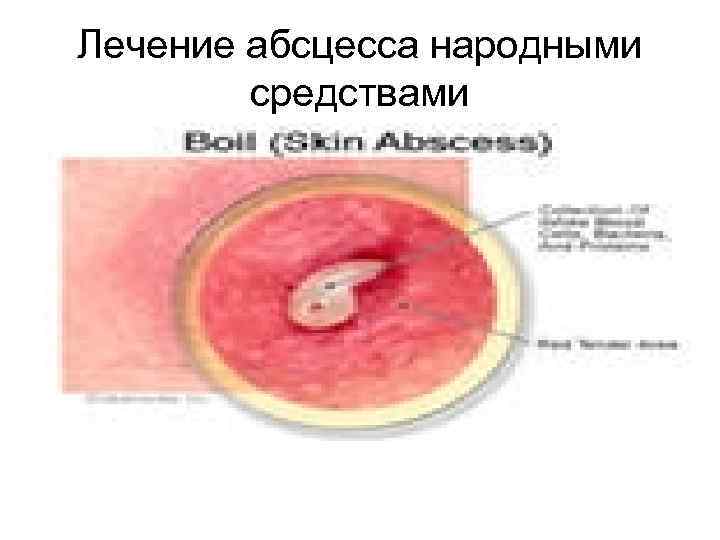

Лечение абсцесса народными средствами